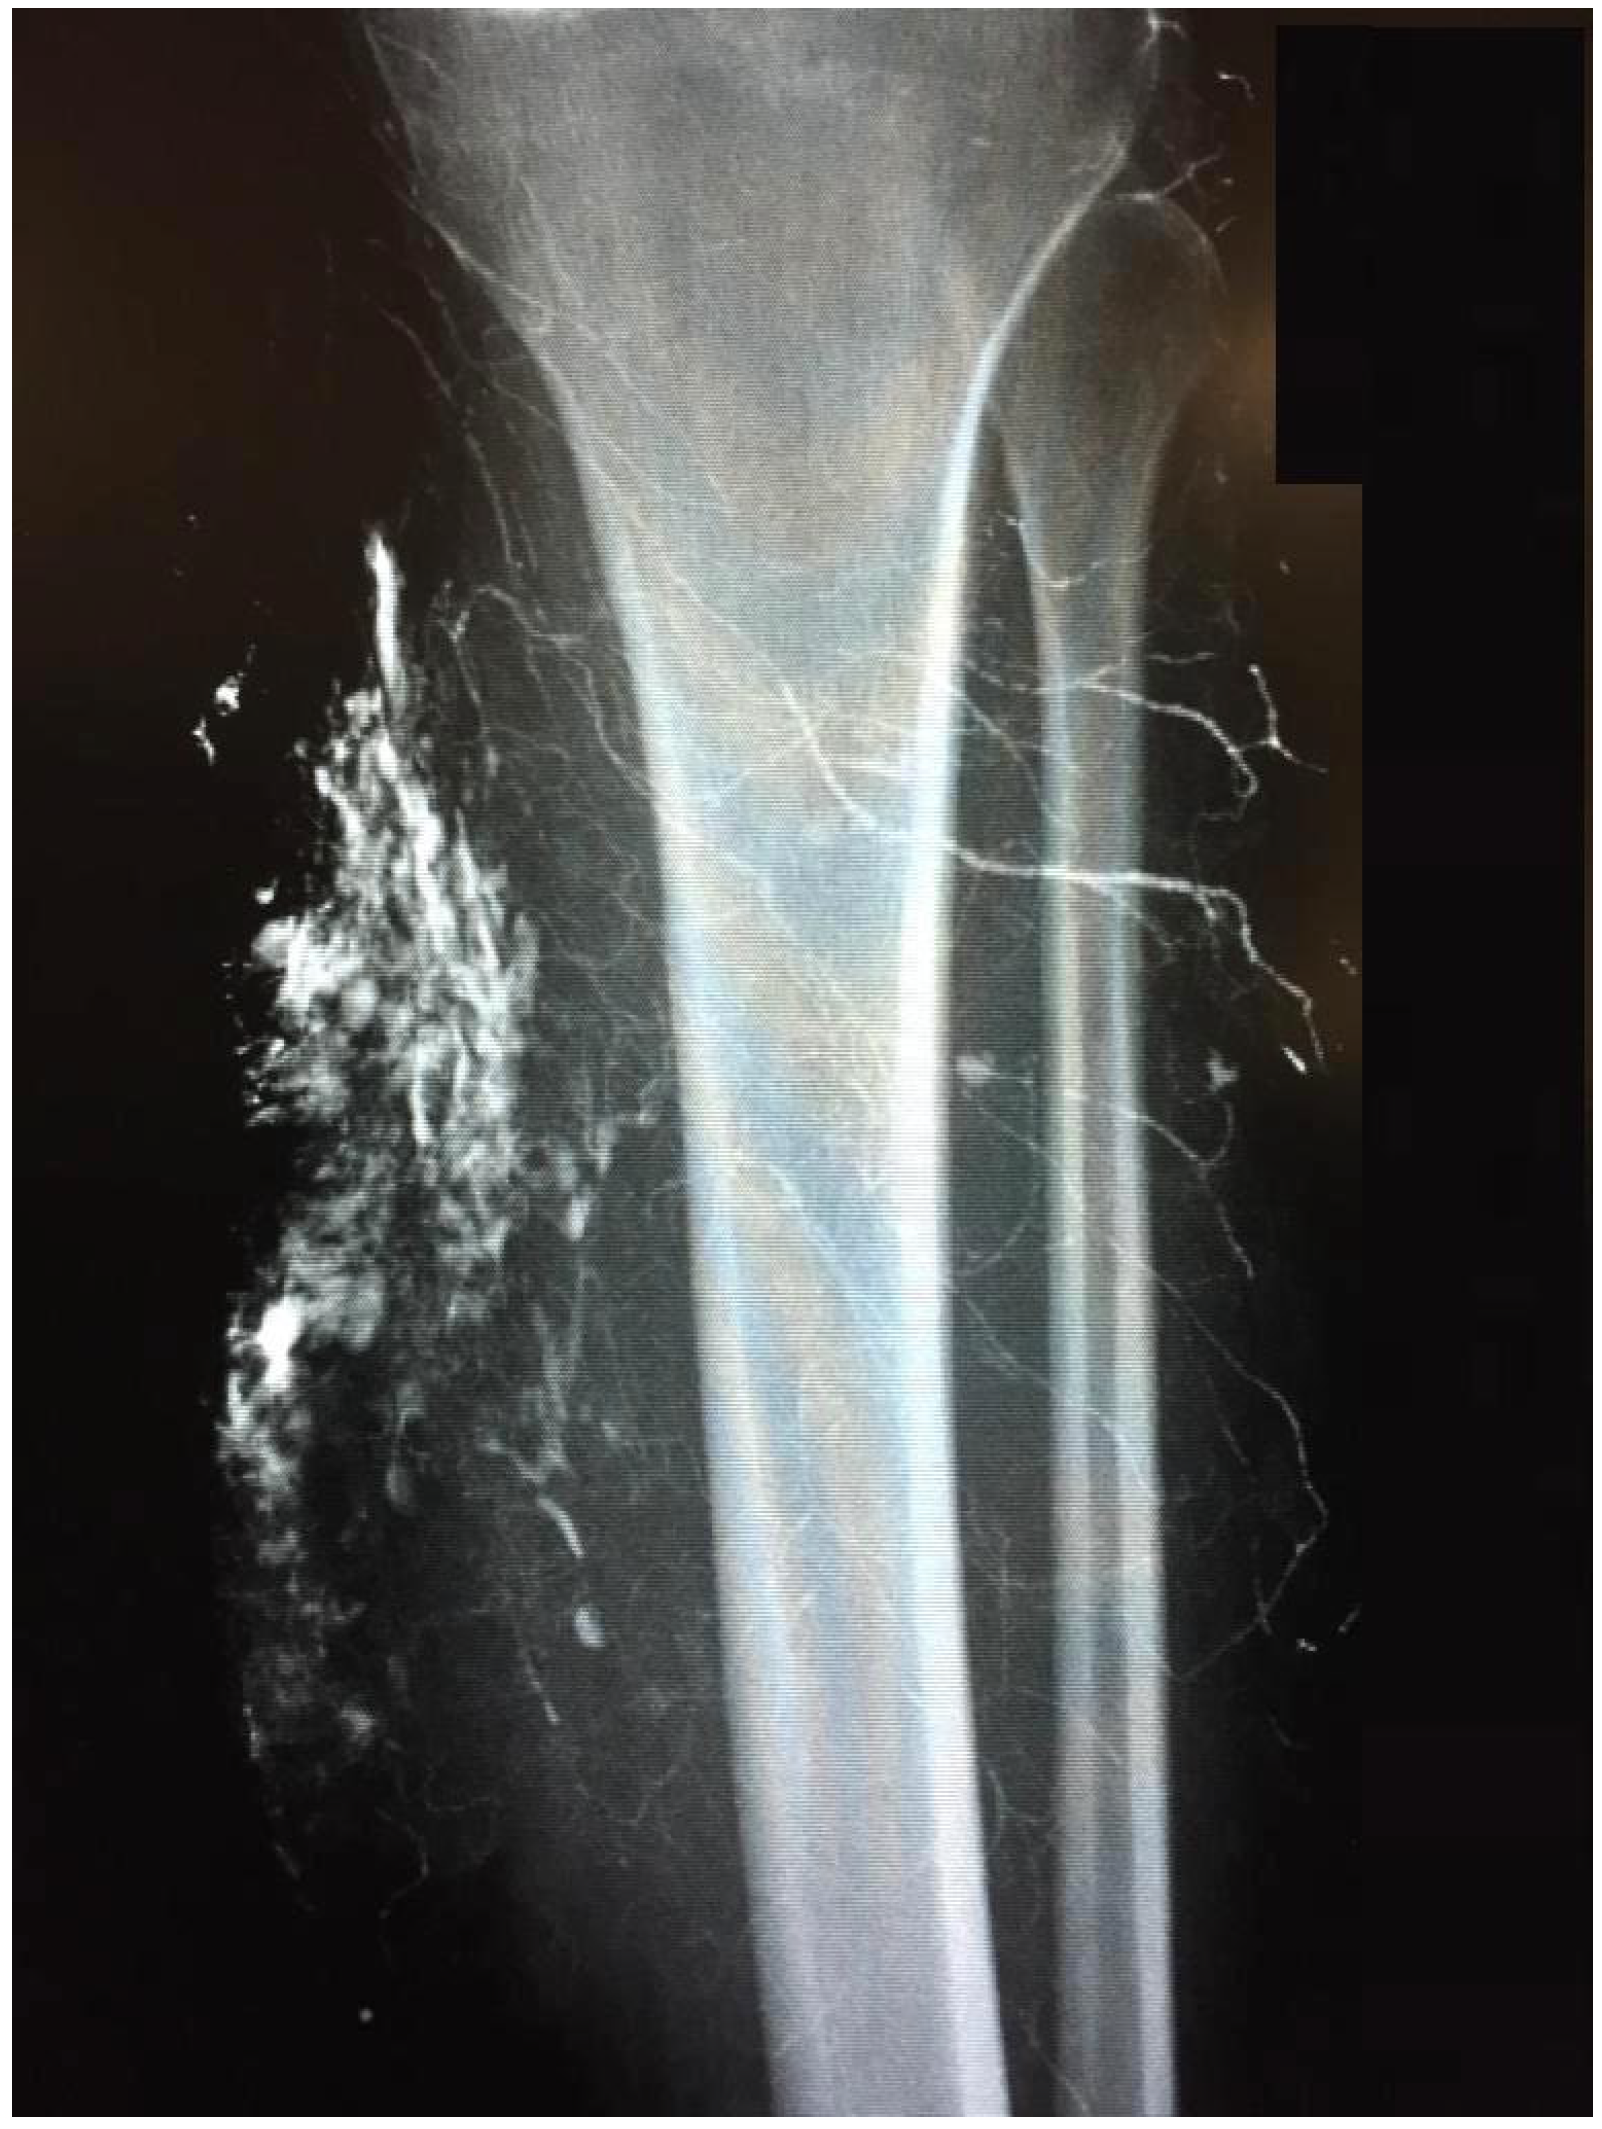

The removed calcifications weighed up to 700 g (Figure 4). The tissue samples were processed microbiologically and histopathologically. An average of three operations was required to achieve healing of the precarious skin conditions. Two patients developed serous retention postoperatively, requiring repeat drainage insertion and vacuum therapy. Improvement could be achieved by systemic antibiotic application appropriate for resistance, vacuum therapy, and additional prolonged drainage therapy over 3–4 days. This treatment included a staged vacuum therapy with initial sanitation of the lesions, subfascial insertion, and immobilization for 5–7 days. In a later operation, closure of the fascia and Prevena™ therapy for 7–10 days was performed. Of note, the adjacent Prevena™ allowed mobilization of the patient with the help of physiotherapy on walking aids. Initially, the focus was on stabilizing elements and gait training. As healing progressed, these measures were expanded to proprioceptive and nociceptive training. The continuous suction treatment reduces tension in the cutaneous and subcutaneous tissue layers and drains wound edema.

Figure 4. Resectate from the thigh (see Figure 2). ©Dr. I. Tarner, Bad Nauheim.